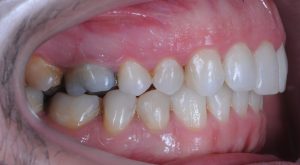

Maloclusión clase II

Se caracteriza por una relación anormal entre los dientes superiores e inferiores, donde los dientes superiores están demasiado adelantados en comparación con los inferiores.

Esto puede generar problemas funcionales, como dificultad para masticar, y también afectar la estética facial.